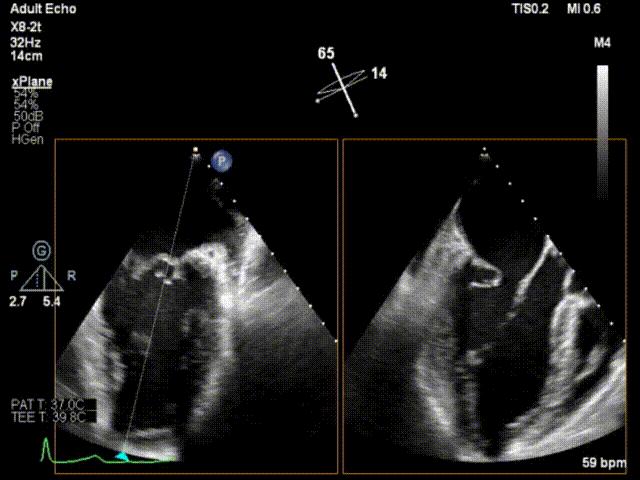

术前超声心动图